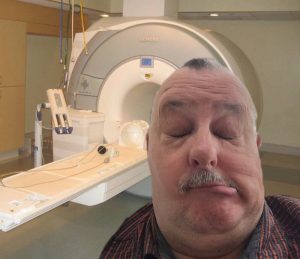

Vandaag 1 juli naar het MCL te Leeuwarden geweest voor een MRI scan van het hoofd. Het is toch weer even wennen als je zo’n apparaat ziet en er in moet. Bij de vorige keer lag ik iets schever en kon zodoende uit het apparaat naar buiten kijken. Nu lag ik platter en zag alleen het binnenwerk. Ik ging met geopende ogen naar binnen en kreeg meteen een claustrofobie aanval. Paniek! Haal mij er onmiddellijk weer uit. Zo gevraagd zo gedaan. Even op adem komen. Ik was ook duizelig. Toch maar weer opnieuw proberen en nu maar met de ogen dicht. Gelukkig dat werkte. En na veel en afwisselend langdurig lawaai van het apparaat zat de eerste ronde erop. Ik kreeg vervolgens een vloeistof ingespoten zodat ze de hersens (als ik die tenminste heb) beter kunnen zien van binnen. Ogen dicht en deze keer duurde het maar drie minuten. Een beetje dronken liep ik de behandelkamer uit op zoek naar mijn vrouw en een lekker bakje koffie.

Vandaag 1 juli naar het MCL te Leeuwarden geweest voor een MRI scan van het hoofd. Het is toch weer even wennen als je zo’n apparaat ziet en er in moet. Bij de vorige keer lag ik iets schever en kon zodoende uit het apparaat naar buiten kijken. Nu lag ik platter en zag alleen het binnenwerk. Ik ging met geopende ogen naar binnen en kreeg meteen een claustrofobie aanval. Paniek! Haal mij er onmiddellijk weer uit. Zo gevraagd zo gedaan. Even op adem komen. Ik was ook duizelig. Toch maar weer opnieuw proberen en nu maar met de ogen dicht. Gelukkig dat werkte. En na veel en afwisselend langdurig lawaai van het apparaat zat de eerste ronde erop. Ik kreeg vervolgens een vloeistof ingespoten zodat ze de hersens (als ik die tenminste heb) beter kunnen zien van binnen. Ogen dicht en deze keer duurde het maar drie minuten. Een beetje dronken liep ik de behandelkamer uit op zoek naar mijn vrouw en een lekker bakje koffie.Nu maar afwachten wat het resultaat van deze scan is. Op 13 juli heb ik weer een afspraak met de Neuroloog.